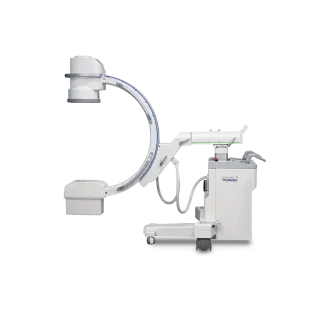

투시장비 C-arm

투시장비 C-arm -